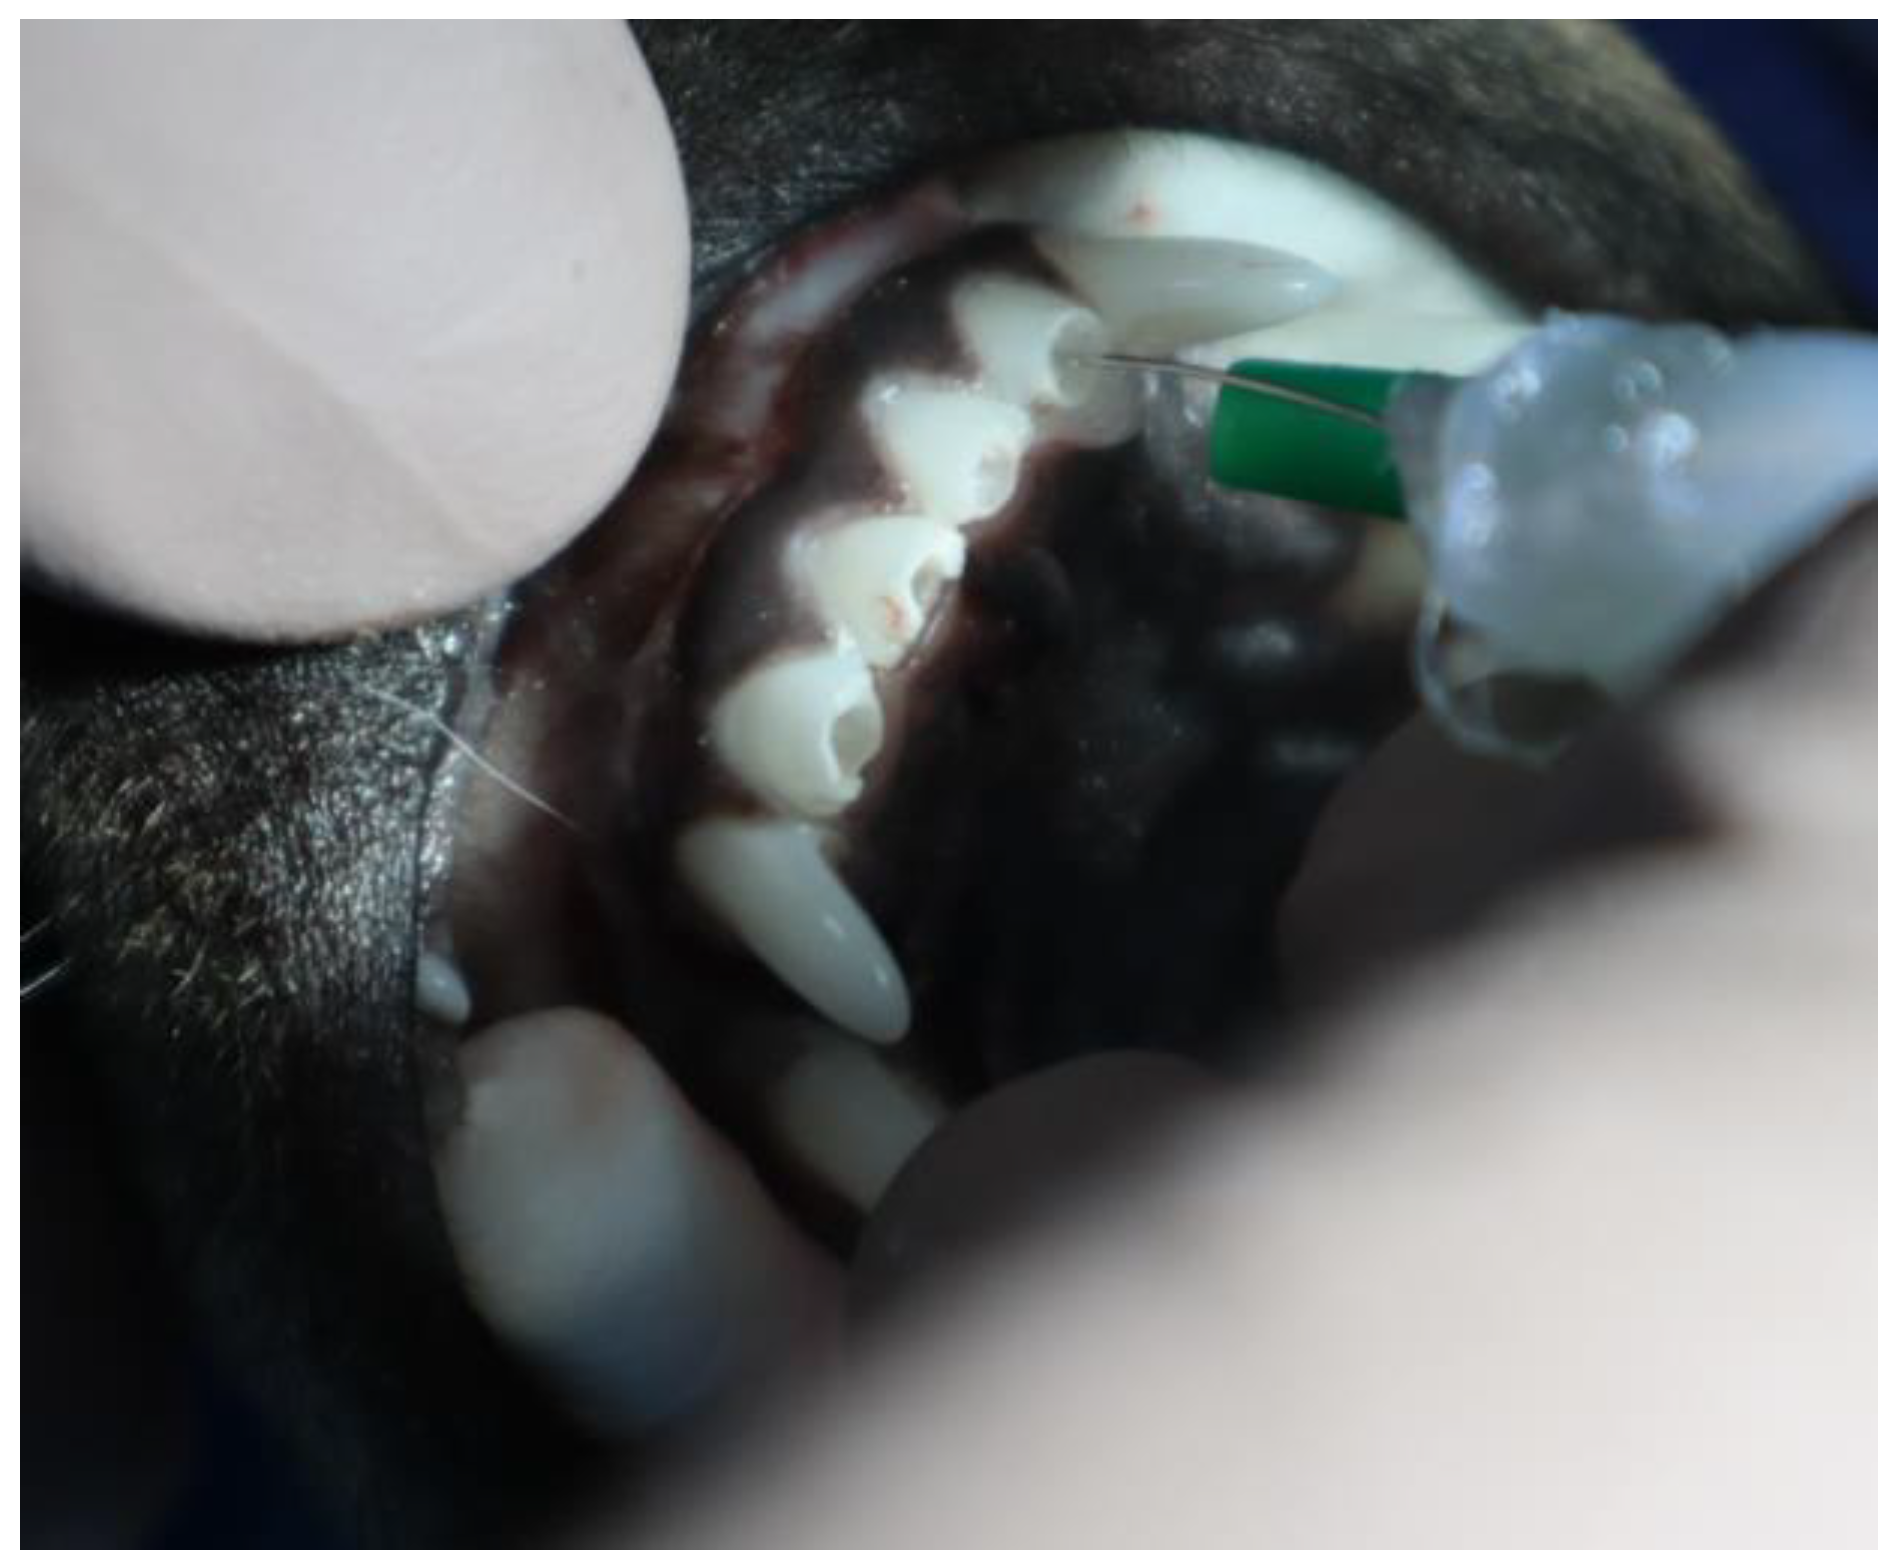

2.2.1. Animal Experiment

2.2.2. X-ray Analysis and Histology